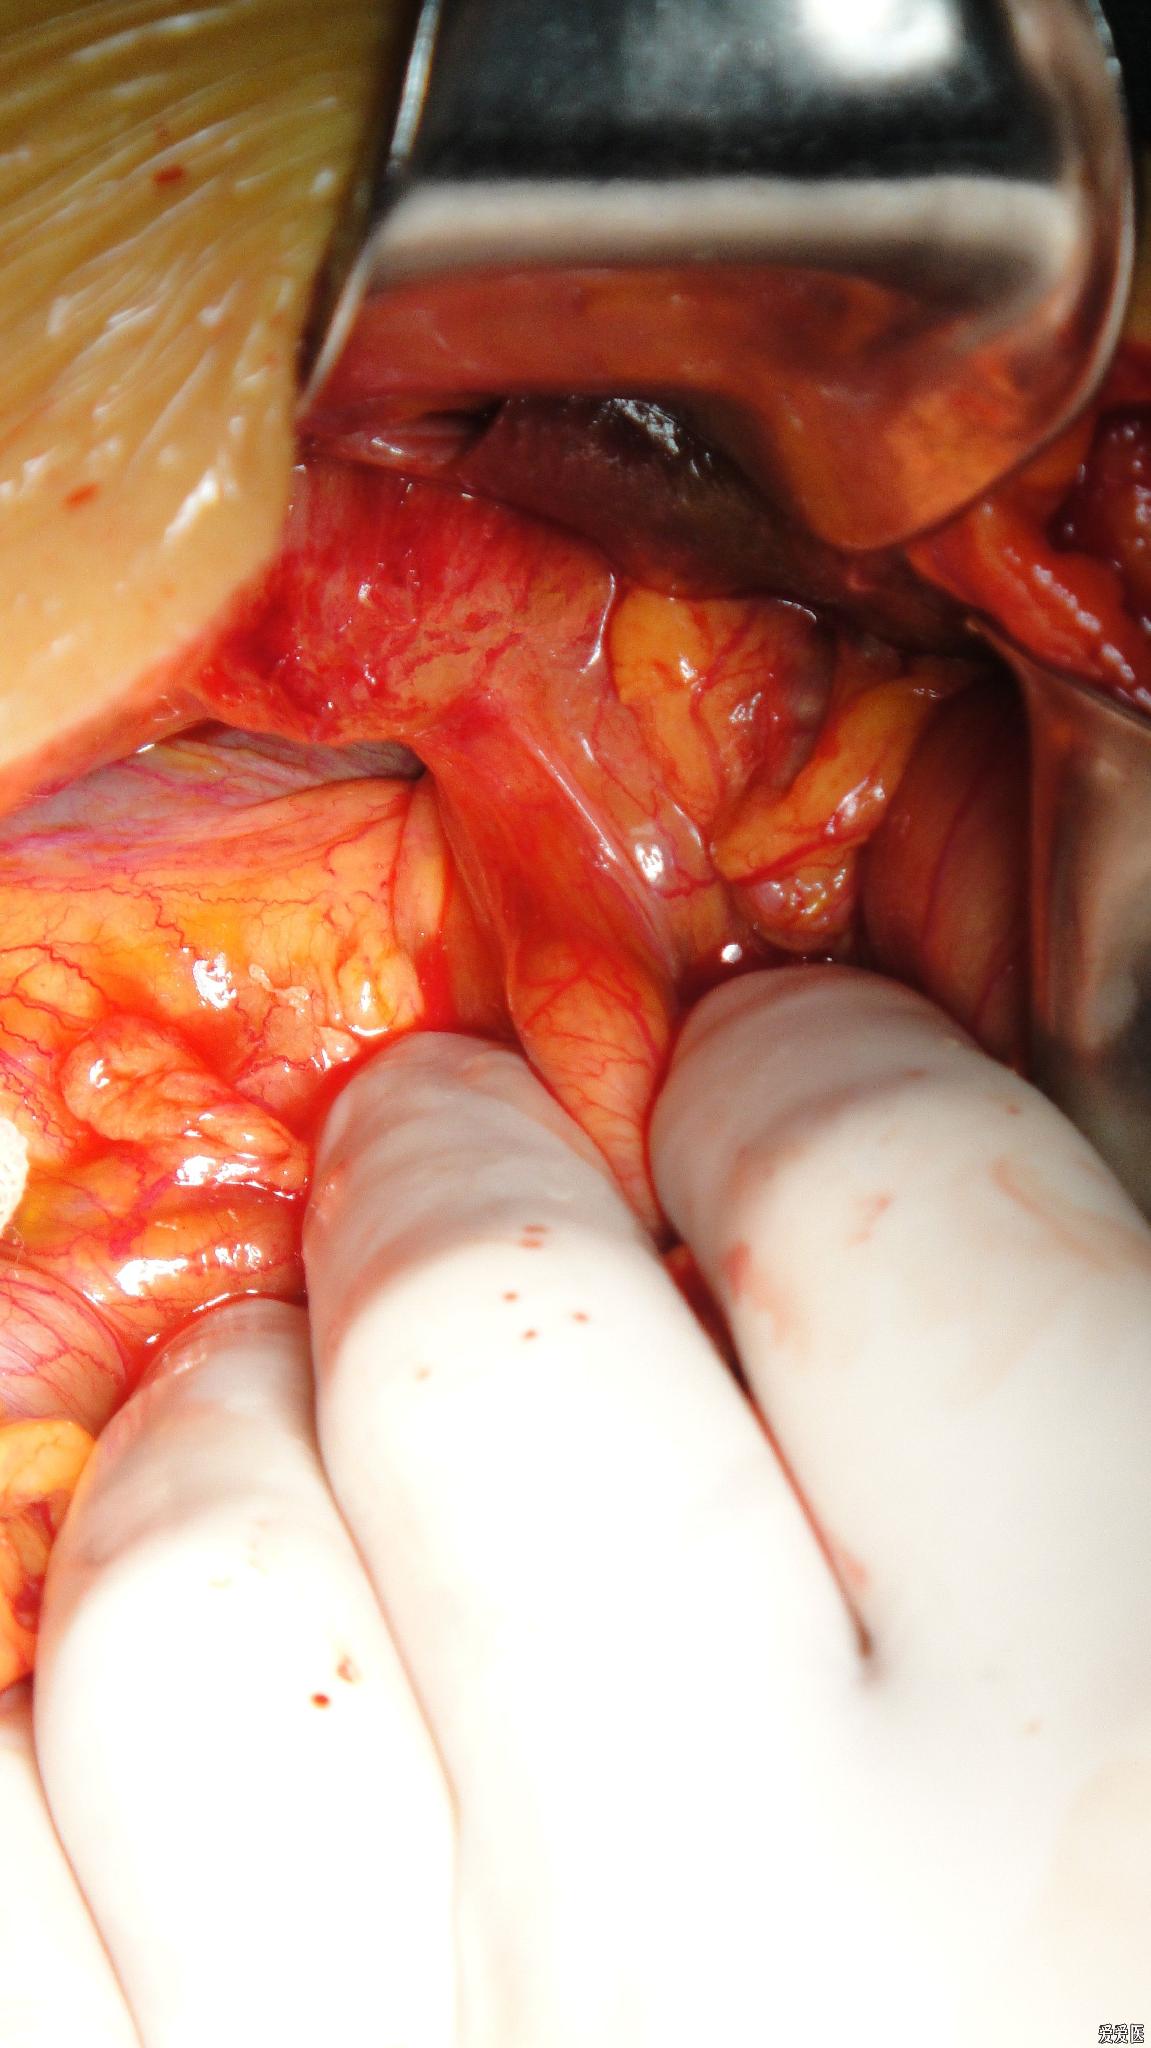

肝門區膽管癌